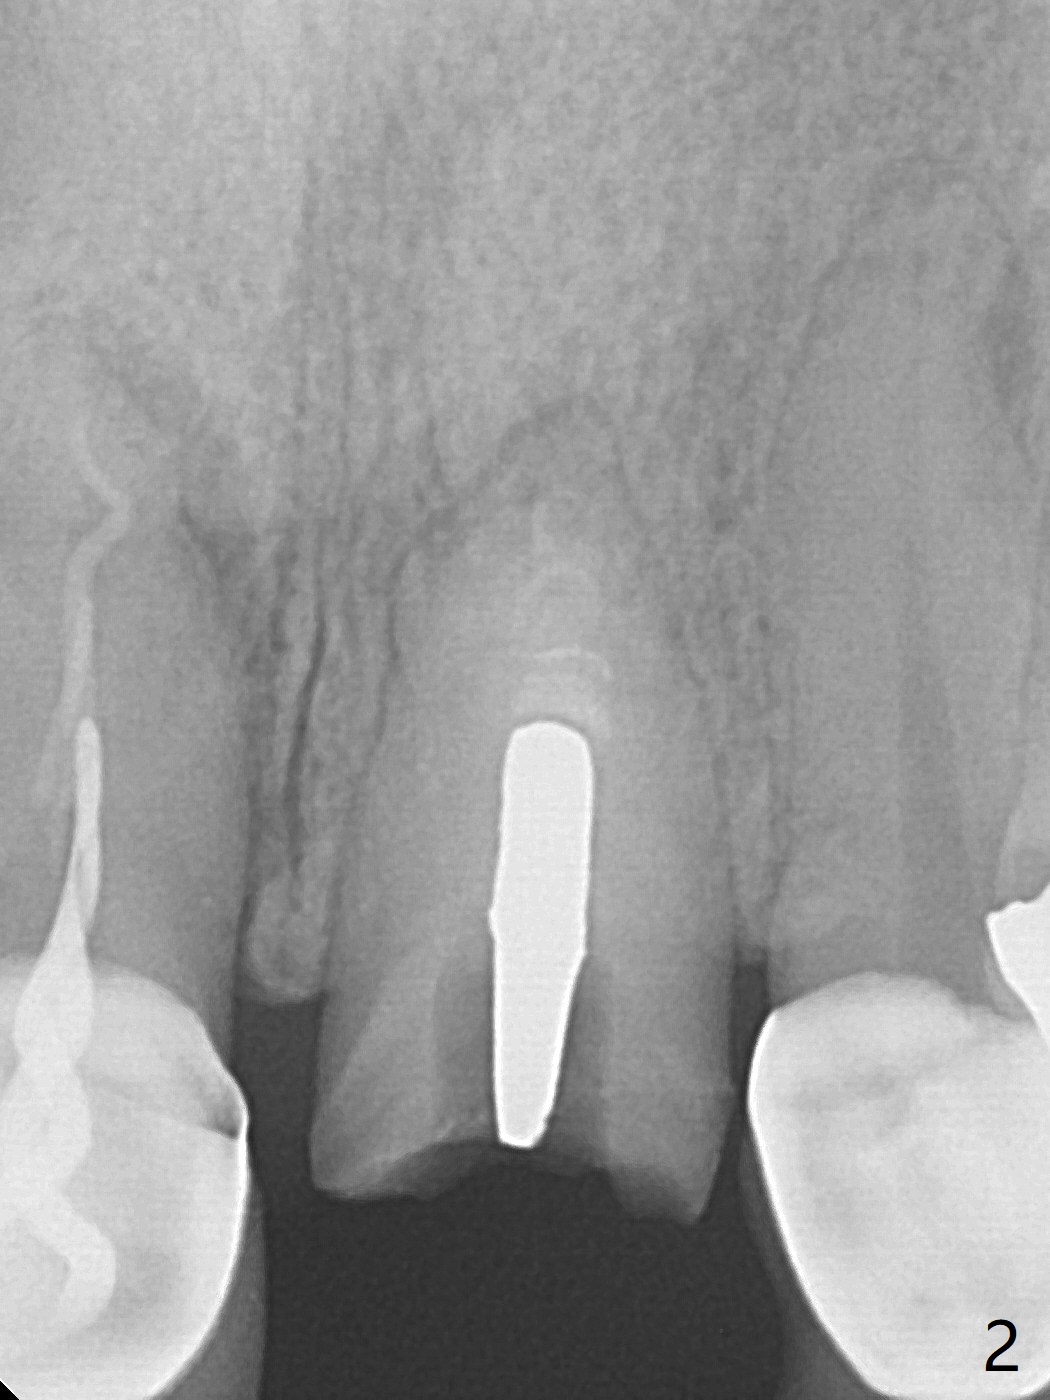

A 51-year-old woman with poor dentition has history repeated dislodged crown and post at #9. Finally the post fracture (Fig.1). After discussion of treatment options, she chooses to save the tooth. Treatment plan is to remove post, possible RCT retreatment, redo post and crown. The post remains stable following lengthy use of Piezo scaler (Fig.2). It appears that Piezo is quite aggressive, removing the tooth structure and the metal. Finally the coronal portion of the post is removed for cast post (Fig.3). There is approximately 2 mm for ferrule effect (Fig.4). The cast post is cemented with RelyX Ultimate and prepared for crown (Fig.5-7).